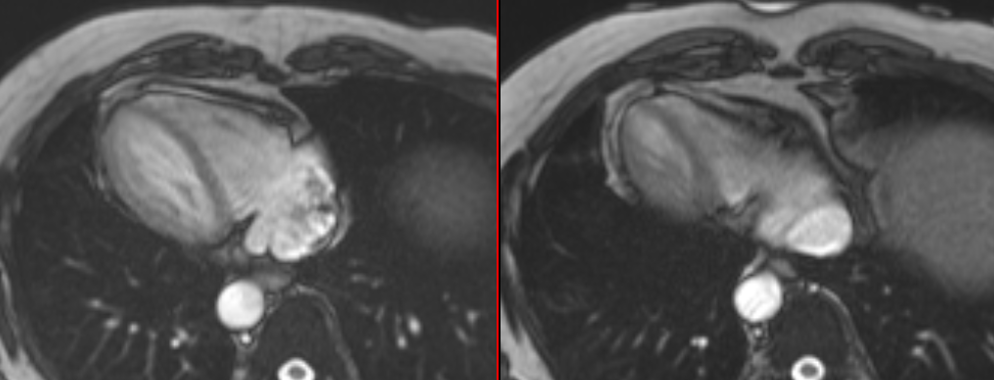

COD 158 - Septum Predominant HCM and RVoTo

RVoTo involvement in HCM is uncommon but diagnosing it may change the management plan and prognosis